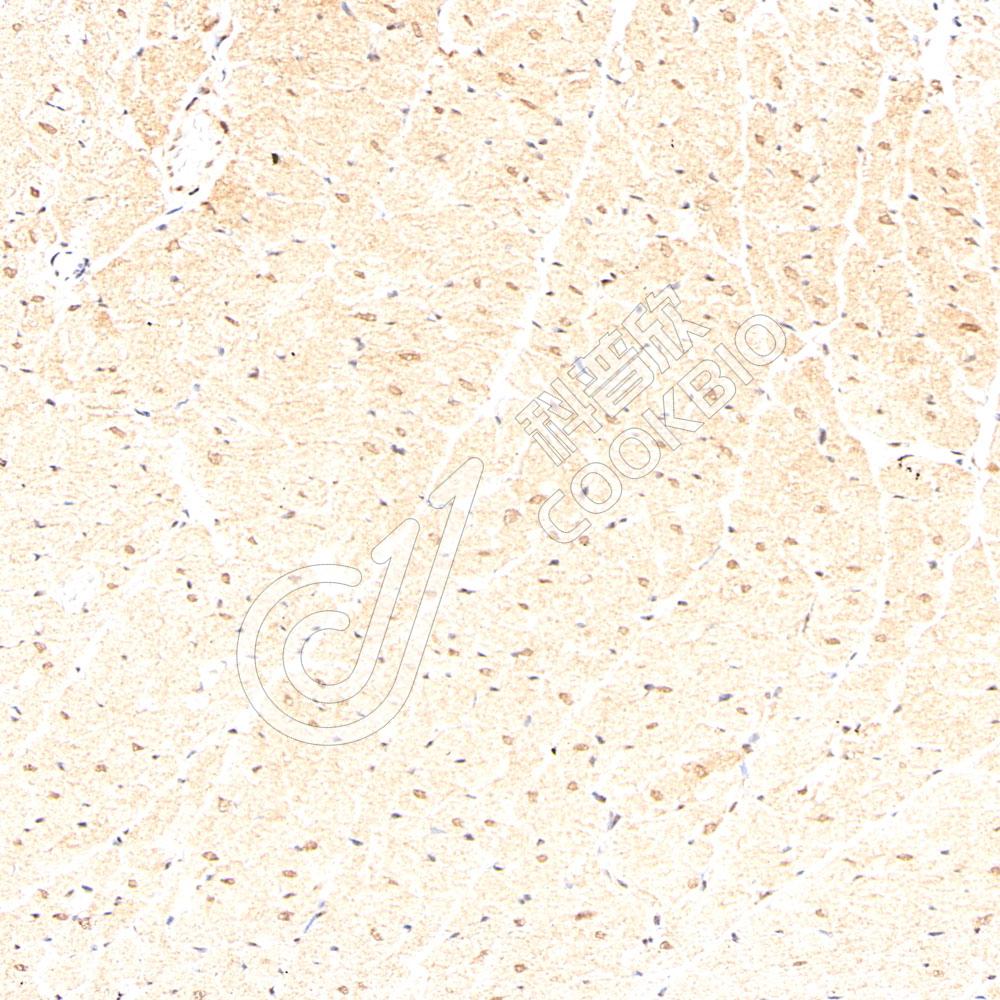

IHC检测Hsp70蛋白(货号 K545732).

样品: 大鼠心脏缺血再灌注损伤, 4%多聚甲醛 (货号KSG1101) 固定12-24小时.

抗原修复: 柠檬酸抗原修复液(干粉, pH 6.0) (KSG1201), 高压锅均匀喷气计时2分钟.

—抗: 1: 800稀释, 4℃ 孵育过夜.

二抗: S-vision免疫组化多聚二抗(山羊抗兔),即用型 (货号KB3906), 室温孵育20分钟.